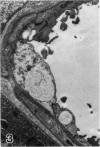

Abundant inflammatory cells such as polymorphonuclear leucocytes and macrophages accumulated and adhered to the endothelial surface of glomerular and intertubular veins and capillaries in rat kidneys after administration of bacterial lipopolysaccharide (LPS). There was also damage to both endothelial cells and proximal tubular cells, including intracytoplasmic oedema, and an increase in the number of lysosomes in the proximal tubular cells in the LPS-treated samples. Immunocytochemistry was used to demonstrate tumour necrosis factor (TNF) and leukotriene (LTR) in both LPS-treated and control samples. Immunoreactive LTR seen in the lysosomes of inflammatory cells attached to the endothelial cell surface may indicate the onset of endothelial cell damage. Positive immunoreactive TNF and LTR were seen on the endothelial cell surface only in the LPS-treated samples, indicating that TNF and LTR may enhance the adhesion of leucocytes to endothelium. Positive reactions of TNF and LTR in lysosomes of the mesangial cells suggest that lysosomes of such cells may be involved in the synthesis and storage of TNF and LTR. In addition to these reaction sites, lysosomes of proximal tubular cells were immunoreactive for LTR. These endogenous LTRs may be implicated in the degeneration of the proximal tubular cells.